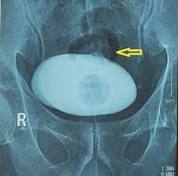

Quảng Ngãi: Bệnh nhân tiểu ra… cọng hành Bệnh nhân Nguyễn Văn L., 60 tuổi, nghề nghiệp: xe ôm; quê quán: Trần Phú - Quảng Ngãi. Bệnh nhân vào BV. Đa khoa Quảng Ngãi lúc 14 giờ ngày ...